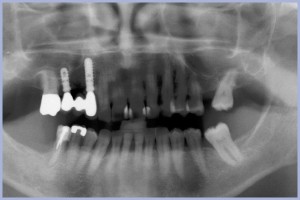

Il terzo case report riguarda una paziente donna di anni 74 sottoposta nel 2007 a trattamento implanto-protesico “full arch” dell’arcata superiore, con procedura di carico immediato, eseguito in tecnica flapless.(9) La paziente era portatrice di una protesi totale mobile nell’arcata superiore, ritenuta soddisfacente dal punto di vista estetico e funzionale, ma non accettata dal punto di vista psicologico. La sua richiesta era di avere denti fissi nel più breve tempo possibile, senza avere dolore. L’esame della ortopantomografia (Fig. 17) evidenziava altezza ossea sufficiente all’inserimento implantare. La TC spirale portata dalla paziente permetteva di evidenziare un osso piuttosto rarefatto, di qualità 3-4 soprattutto nei settori posteriori, ma volumi ossei sufficienti al posizionamento implantare in tecnica flapless (Fig. 18). Il piano di trattamento, rivolto a soddisfare le richieste della paziente, ha previsto una protesi implanto-supportata “full arch”, a carico immediato, eseguita in chirurgia flapless sotto sedazione vigile. Il fattore di rischio relativo alla scarsa qualità ossea è stato affrontato aumentando il numero degli impianti (sono stati posizionati 10 impianti) e utilizzando la massima lunghezza possibile in relazione al sito. Inoltre la paziente non richiedeva al momento una riabilitazione delle selle edentule posteriori inferiori e quindi gli impianti posteriori inseriti in osso di scarsa qualità venivano risparmiati dal carico diretto. La programmazione del caso è avvenuta mediante l’utilizzo di una mascherina radiologica, costruita dopo ceratura diagnostica, che ha permesso di valutare le corrette distanze mesio-distali dei siti implantari. Il mappaggio della mucosa ha permesso di evidenziare gli spessori della mucosa nei vari siti implantari. Le misure dello spessore mucoso sul versante vestibolare, crestale e palatale dei vari siti implantari sono state sottratte allo spessore totale del modello in gesso così da evidenziare il reale spessore osseo disponibile. Queste indicazioni hanno guidato il corretto posizionamento degli analoghi implantari sul modello in gesso. Dal modello in gesso è stata ricavata una mascherina chirurgica che ha guidato la fresa pilota iniziale nella preparazione flapless (Fig. 19). La preparazione flapless è stata perfezionata mediante osteotomi. L’inserimento dei transfer e la relativa impronta hanno permesso la costruzione in laboratorio di un modello di lavoro che riproduceva l’esatta posizione implantare. Su tale modello sono stati inseriti i monconi in titanio pieno fresati al parallelometro. Quindi è stato preparato un provvisorio in composito su struttura metallica di sostegno. A 24 ore dall’intervento chirurgico si è provveduto alla consegna della protesi circolare provvisoria. Il quadro clinico era nettamente favorevole: nessun sanguinamento, assenza di edema, dolore trascurabile. Si è proceduto all’inserimento dei monconi tramite battitura con apposito percussore (Fig. 20) e si è cementata la protesi con cemento provvisorio Temp Bond (Fig. 21). L’ortopantomografia immediatamente successiva ha permesso di controllare il fitting protesico sugli impianti (Fig. 22). L’estetica e la funzionalità hanno soddisfatto la paziente. In 26 ore si è completata la procedura di carico immediato. A distanza di 6 mesi il provvisorio è stato sostituito da una protesi circolare definitiva in oro-ceramica. Sono state eseguite le varie valutazioni funzionali ed estetiche ed è stato eseguito un controllo radiografico (Fig. 23). Nel tempo la paziente è stata seguita mediante controlli periodici, includenti igiene professionale. Il controllo estetico, clinico e radiologico nel 2014, dopo quasi 7 anni (Figg. 24-26), permette di constatare un mantenimento dei livelli tissutali e dell’estetica nel tempo. Non si sono verificate complicanze implantari e/o protesiche. La paziente manifesta la sua soddisfazione per il trattamento eseguito.

- Fig. 23 – Immagine radiologica della protesi definitiva in sede

- Fig. 24 – Controllo clinico a 7 anni

- Fig. 25 – Controllo radiografico a 7 anni